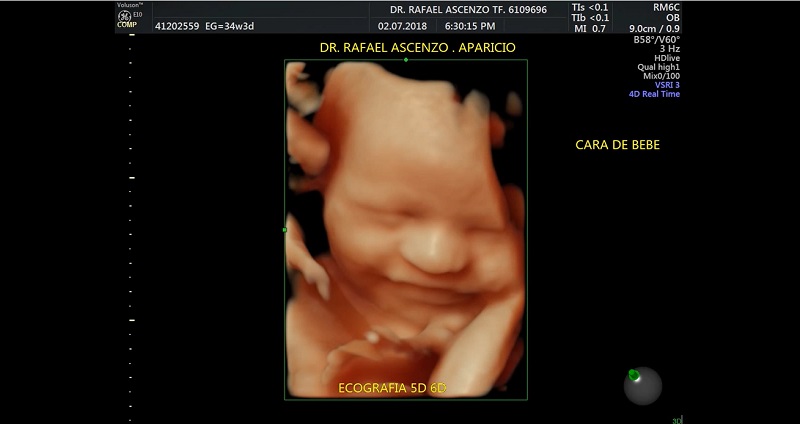

Hoy existe tecnología avanza y con ello se puede lograr muchas cosas en favor de la salud. La imagen muestra una ecografía 6D ha captado la sonrisa de un bebé dentro del vientre materno